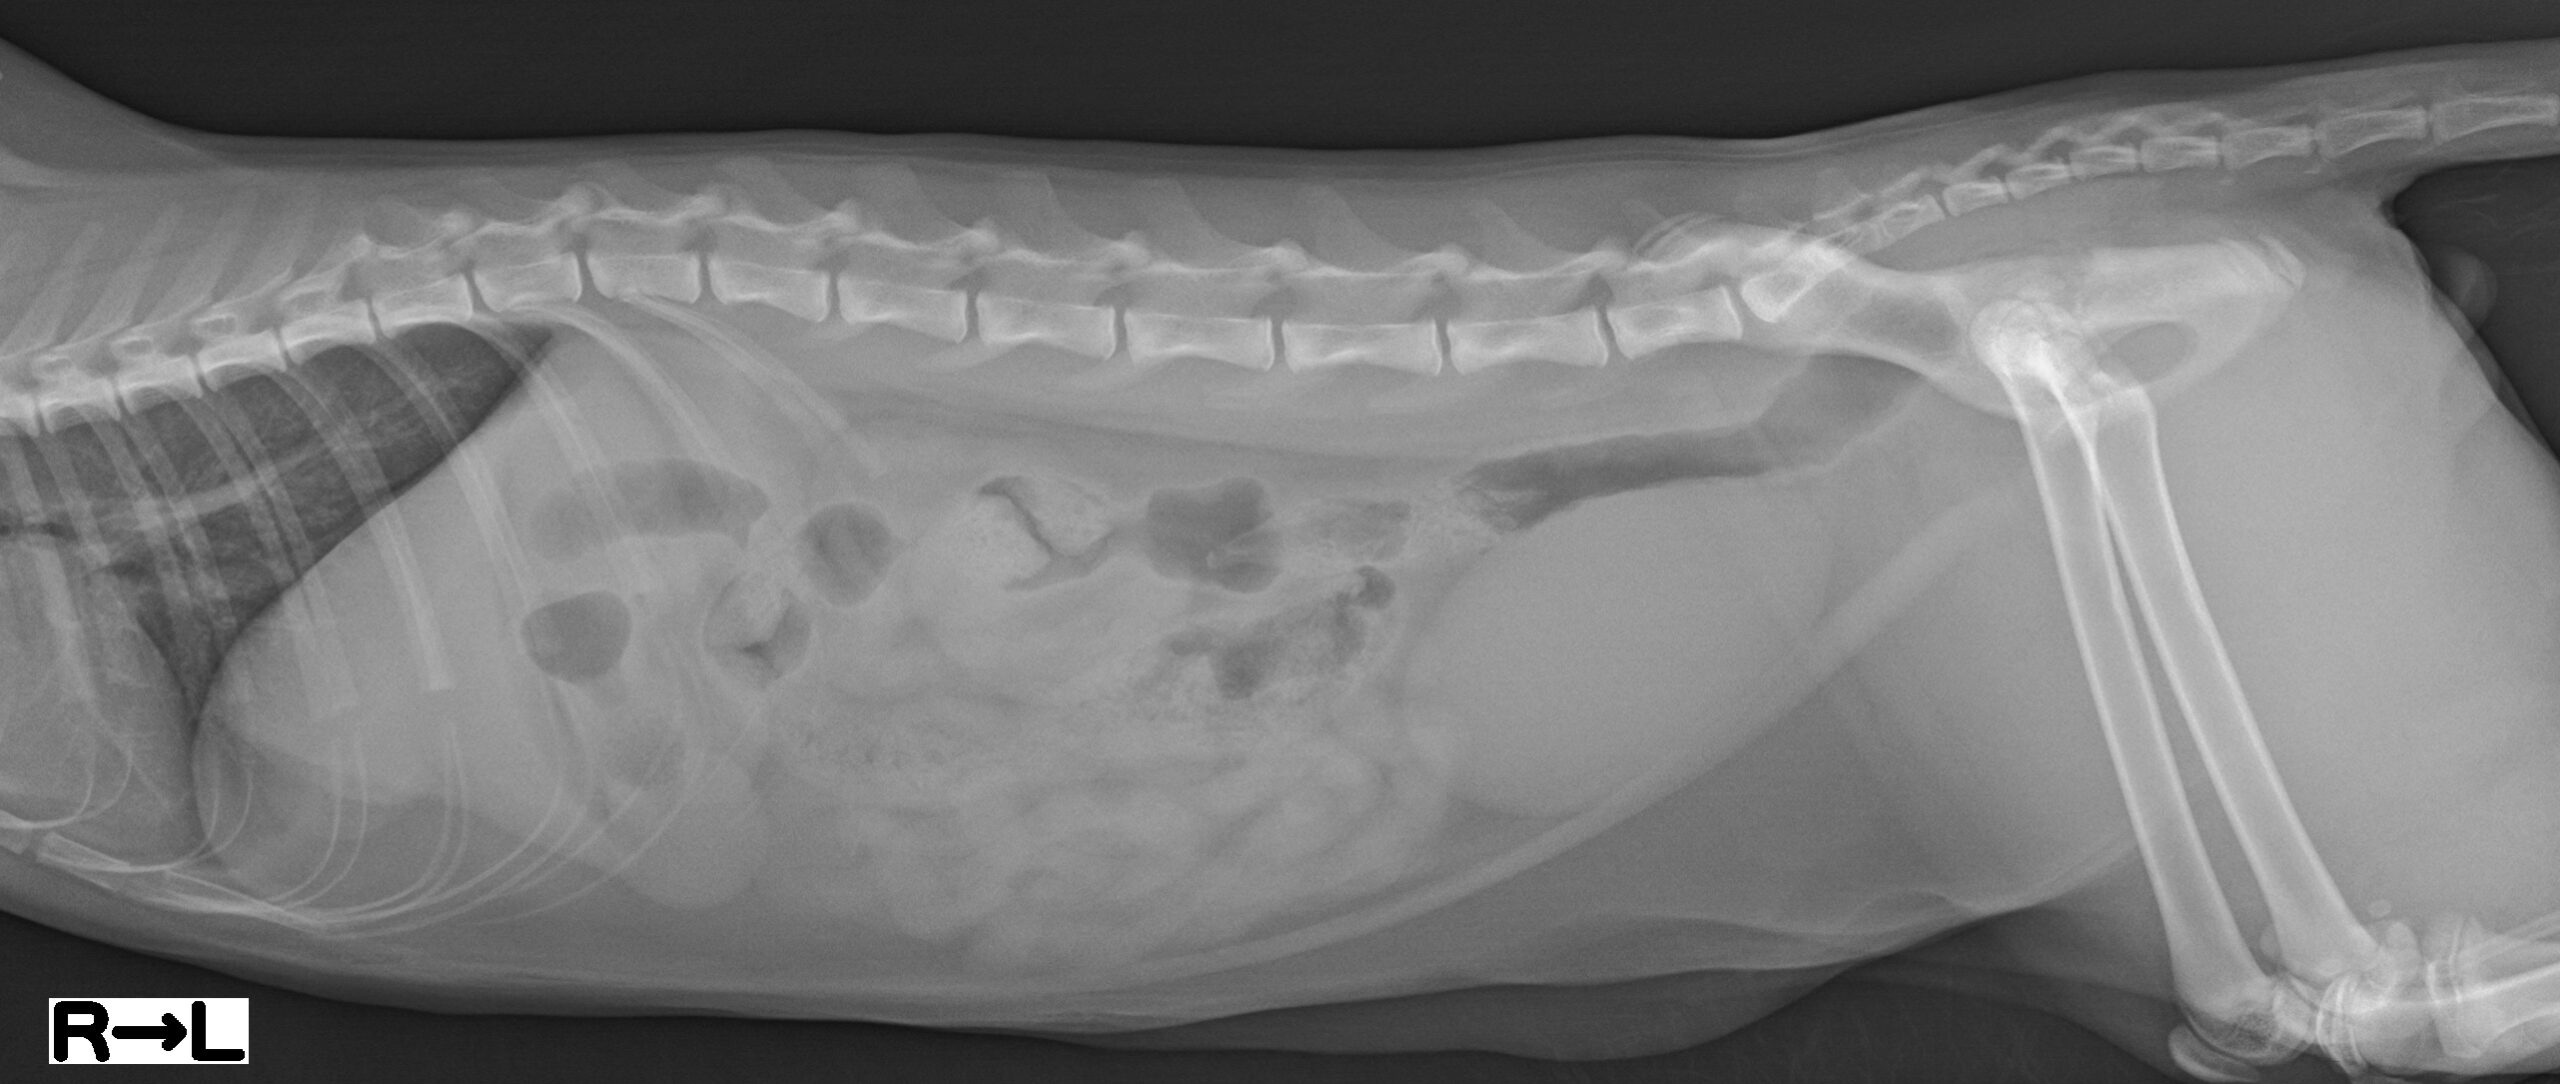

犬の横隔膜ヘルニアに対し整復術および脾臓摘出を実施した1例の画像

2026.02.20

犬の横隔膜ヘルニアに対し整復術および脾臓摘出を実施した1例

• 呼吸器部門

• 麻酔管理部門

• 軟部外科部門

• 画像診断部門

• 岩田 泰介